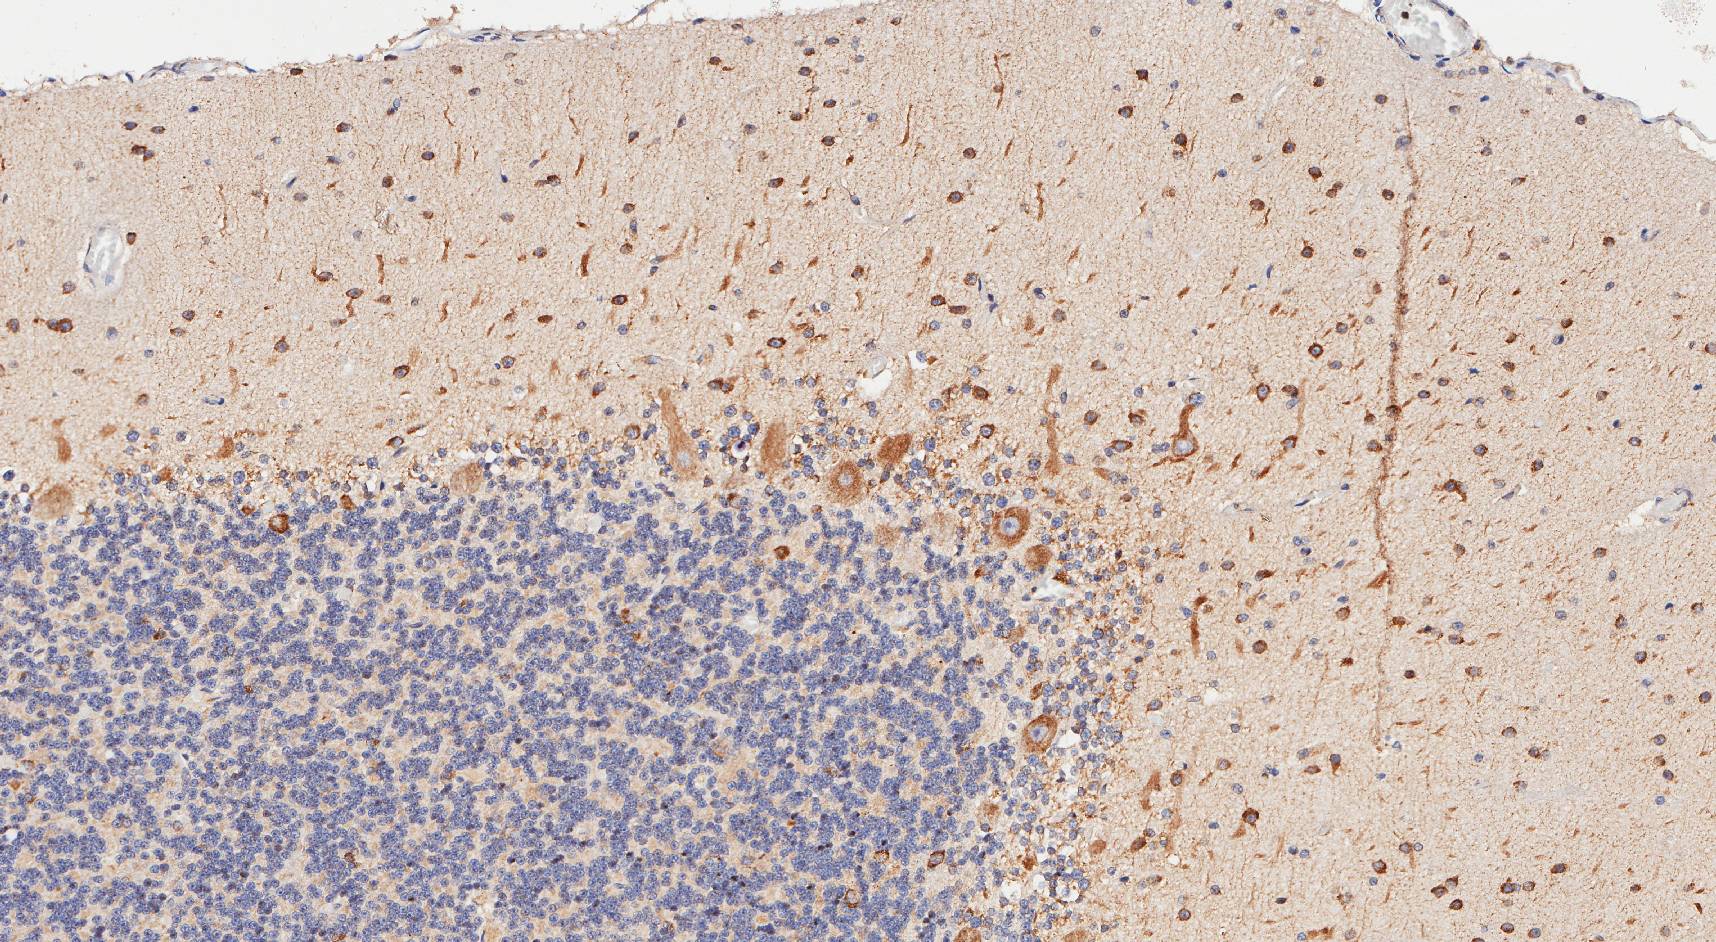

purkinje March 30, 2020 Return to: You can learn a lot by looking – cool pics from our recent workFull resolution (1716 × 942) Image navigation Previous Image Next Image Share this: Share on Facebook (Opens in new window) Facebook Share on X (Opens in new window) X More Share on WhatsApp (Opens in new window) WhatsApp Share on LinkedIn (Opens in new window) LinkedIn Share on Pinterest (Opens in new window) Pinterest Share on Telegram (Opens in new window) Telegram Share on Reddit (Opens in new window) Reddit Like Loading...